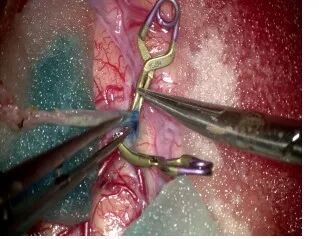

手术过程

10-0缝线缝合S T A-M C A

吻合血管

缝合后